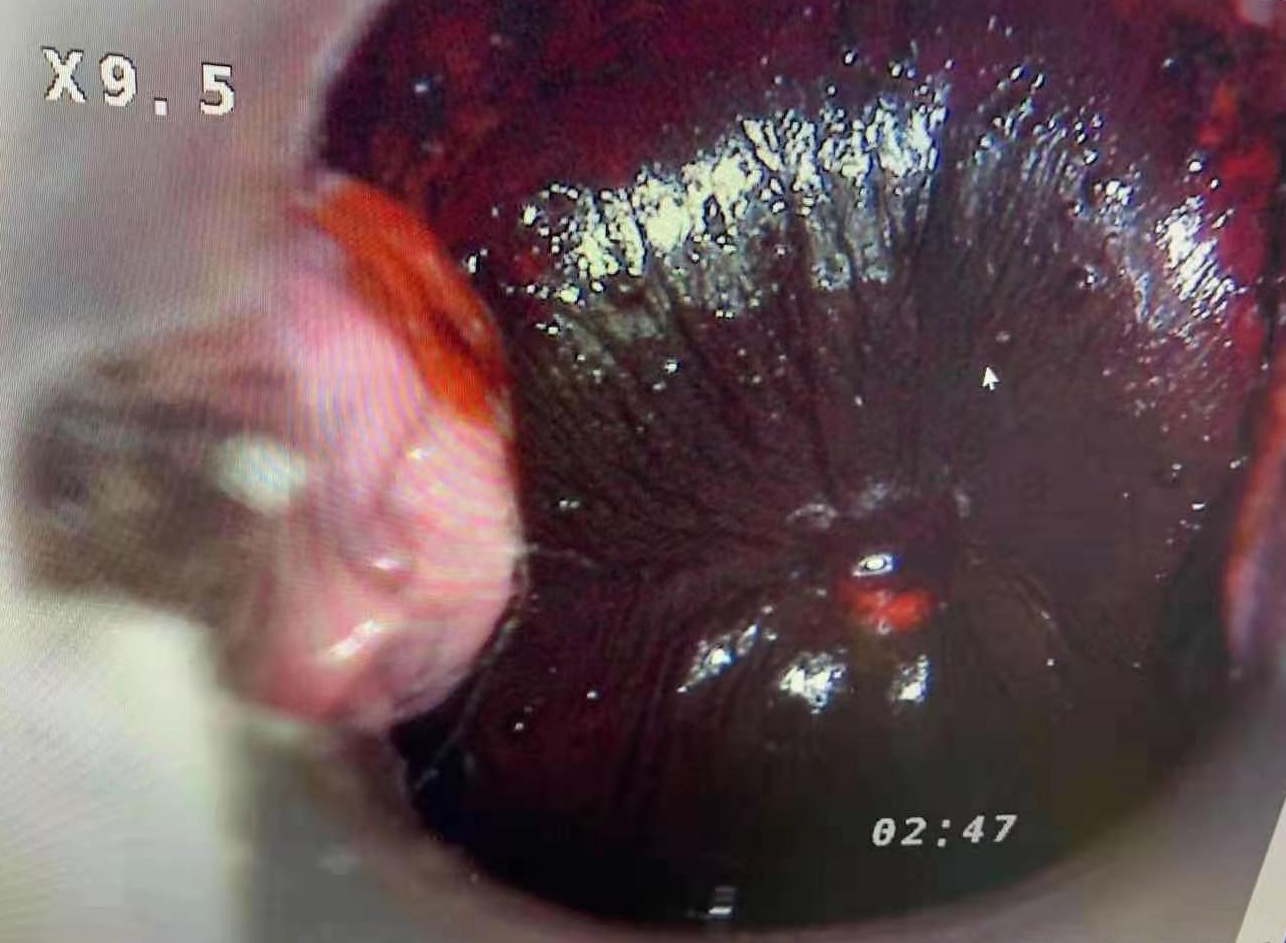

**Extra long depth of field, super large field of view, super three-dimensional sense, realistic color reproduction, unique light path design, providing true 3D visual effects for pre-cancerous, pre-lesional punctiform vessels, columnar epithelium and some tiny lesions .

**50times System Magnification ,17 times optical amplication,3 times Digital amplification.able to output divine clear view of the examination lesion parts. Provide doctors with 3D visual image of the epithelial tissues,and different levels of the blood vessels. **LED light source,lifespan more than 20,000hours. **Horizontal Resolution up to 2064.

Real cervical diagnosis pictures